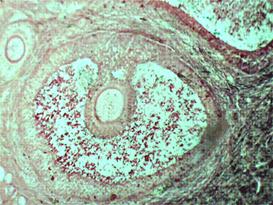

Рис. 27–28. Яйцеклетка в яичнике млекопитающего: 1 ядро; 2. ядрышко; 3. цитоплазма. Граафов пузырек

На микропрепаратах найти овогонии и фолликулы различной степени зрелости (первичной, созревающей и зрелой). Изучить зрелый фолликул – граафов пузырек.